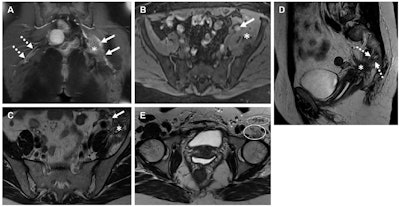

Spectrum of imaging features of nerves involved in endometriosis in three women. (A) Coronal T1W contrast-enhanced MR image in a 44-year-old woman shows a thickened left sciatic nerve with increased enhancement (solid arrows) and a fibrotic mass (*). The right-side sciatic nerve is normal in appearance (dashed arrows). (B-D) Axial T1W image (without contrast enhancement) with fat saturation (B) in a 43-year-old woman shows a cystic endometriotic lesion with signal hyperintensity (arrow in B). The adjacent left iliacus muscle is asymmetrically thickened due to involvement by endometriosis (* in B). Axial T2-weighted MR image (C) at the same level as B shows T2 shading in the cystic lesion (arrow in C) and a fibrotic mass replacing the iliacus muscle (* in C). Sagittal T2-weighted MR image (D) shows the sacral nerve roots (dashed arrows in D) encased by a fibrotic endometriotic mass (* in D). (E) Axial T2-weighted MR image in a 37-year-old woman shows atrophy of the left iliopsoas (solid oval) and sartorius muscles (dashed oval), both innervated by the femoral nerve. Images and caption courtesy of the RSNA.